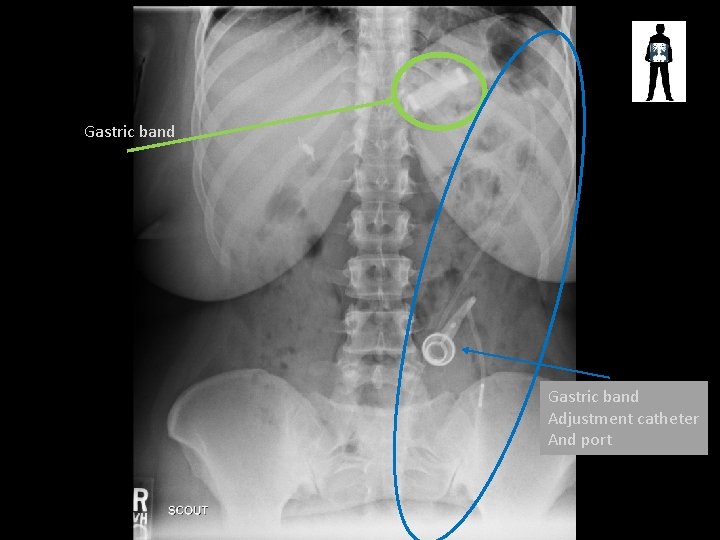

Gastric band Adjustment catheter And port